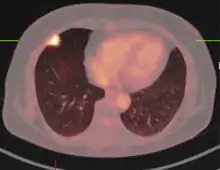

FDG-PET study of a 71-year-old woman with a solitary pulmonary nodule (thin arrow) in the left lower lobe near the heart. The scan also revealed abnormal increased activity at the gastro-esophageal junction (thick arrow). The final diagnosis was non-Hodgkin lymphoma at both sites.

If there is an intermediate risk of malignancy, further imaging with positron emission tomography (PET scan) is appropriate (if available). It can be done simultaneously as a CT scan in the form of PET-CT. Around 95% of patients with a malignant nodule will have an abnormal PET scan, while around 78% of patients with a benign nodule will look normal on PET (this is the test sensitivity and specificity).[15] Thus, an abnormal PET scan will reliably pick up cancer, but several other types of nodules (inflammatory or infectious, for example) will also show up on a PET scan. If the nodule has a diameter of less than one centimeter, PET scans are often avoided because of an increased risk of falsely normal results.[15][16][17] Cancerous lesions usually have a high metabolism on PET, as demonstrated by their high uptake of FDG (a radioactive sugar).